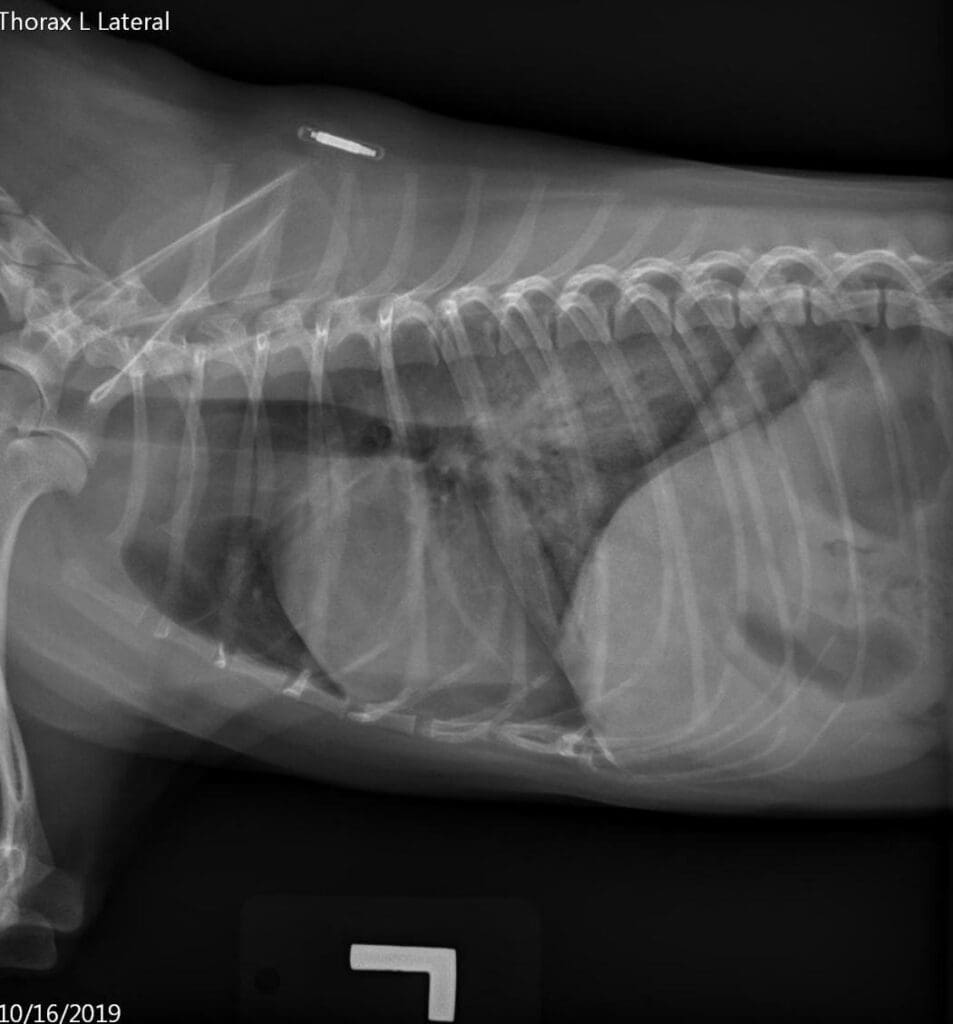

Left lateral view of the thorax 4 hours after the blood transfusion

Our patient had acutely-developed bilateral infiltrates, received a blood transfusion within 6 hours prior to the onset of clinical signs and was likely severely hypoxemic. No heart murmur or left atrial enlargement was evident on physical examination and thoracic imaging, therefore a cardiogenic origin of pulmonary infiltrates is deemed unlikely.